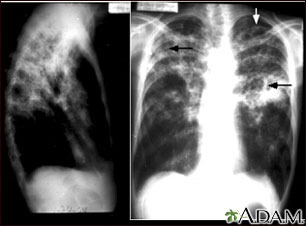

- Chest CT scan

- Chest x-ray

Symptoms often improve in 2 to 3 weeks after starting treatment. A chest x-ray will not show this improvement until weeks or months later. The outlook is excellent if pulmonary TB is diagnosed early and effective treatment is started quickly.